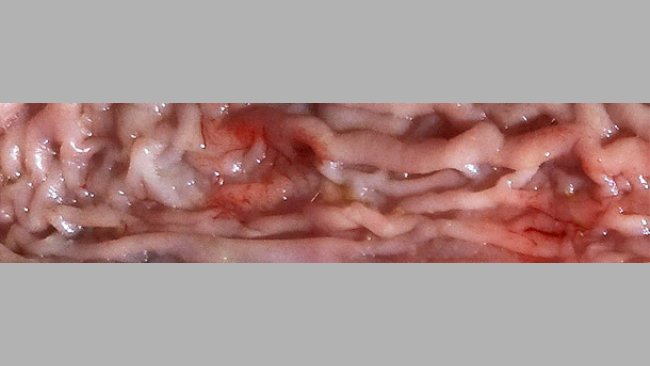

Ileitis can take different forms, and it is frequent that a subclinical and a more severe and clinical form coincide.